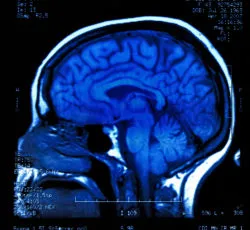

Dilantin works by slowing down electric signals in the brain, which prevents the onset of seizures. Even though Dilantin has helped numerous patients with epilepsy, this drug has been linked to serious side effects like cerebellar atrophy. Also known as focal cerebral atrophy, this condition is described as atrophy or deterioration of the cerebellum.

The cerebellum is part of the brain that is under the cerebrum, which is behind the brain stem. The cerebellum regulates evolutionary functions like posture and movement, allowing the patients to talk and walk smoothly. When the cerebellum deteriorates, the patient can experience symptoms interfering with their ability to speak and move including: